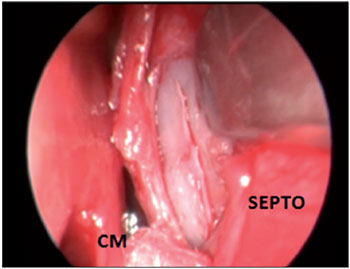

CASE STUDY #2A 35-year-old female patient sought advice from the Specialized Service in Otolaryngology in August 2010, complaining of a localized headache, cacosmia, and nasal obstruction with progressive worsening of her symptoms during the previous 6 months. Her symptoms had remained after drug treatment with amoxicillin and clavulanate potassium for 10 days. Video-endoscopy showed a deviated septum and inferior turbinate hypertrophy. A CT scan of the paranasal sinuses and nasal cavity in the axial, coronal, and sagittal planes with a bone window of 2500-3500 rads was requested, which identified pneumatization of the crista galli apophysis with signs of mucosal thickening and obliteration interiorly. We introduced antibiotic treatment (levofloxacin at a dose of 500 mg/day) for 14 days, corticosteroids (prednisone at a dose of 40 mg/day) for 7 days, and symptomatic analgesia. The patient's symptoms improved temporarily, but 5 days after treatment with antibiotics was stopped, recurrence of her symptoms occurred. A second CT scan of the paranasal sinuses and nasal cavity showed the maintenance of mucosal thickening and obliteration within the crista galli (Figure 3). Endoscopic surgery by a transseptal approach through the right nostril was indicated for drainage and cleaning of the pneumatized crista galli (Figures 4-7).

Figure 4. Intraoperative endoscopic visualization of the right nasal cavity showing septal incision and detachment.

SEPTO = nasal septum; CM = middle turbinate.

Figure 5. Intraoperative endoscopic visualization of the right nasal cavity demonstrating septal resection to allow approach to the bone wall of the pneumatized crista galli.

SEPTO = nasal septum; CM = middle turbinate.